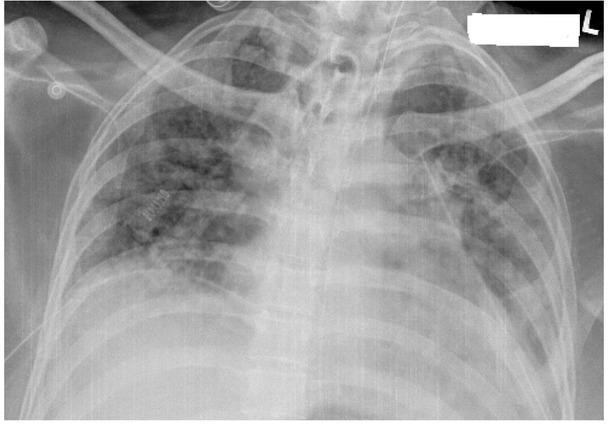

Fig. 1A

Fig. 1B

Fig. 1C

Fig. 2A

Fig. 2B